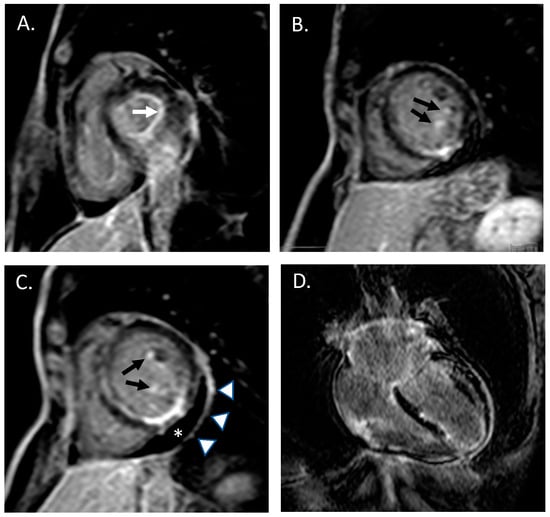

She had a medical history of severe asthma with forced expiratory volume in the 1st second (FEV1) < 50% of the predicted value and three years before she underwent surgery for nasal polyposis. She denied any cardiovascular risk factors, as well as smoking, alcohol assumption or any illicit drug injection. Three months before, she received the second dose of the BNT121b1 mRNA SARS-CoV2 vaccine. The patient did not report any history of fever, night sweats, unintentional weight loss, dyspnea, gastrointestinal symptoms, joint pain, myalgia or cutaneous manifestations. She reported intermittent use of non-steroidal anti-inflammatory drugs (NSAIDs) for recurrent episodes of headache. Laboratory tests, performed at Emergency department, showed a mild increase of high sensitivity cardiac troponin (hs-TnI 48 ng/L, 99th percentile upper reference limit 14 ng/L) and increased eosinophil count (2080/mm3, 19.5%, total blood cell count 10.68 × 103/microL). Serum creatinine, thyroid enzymes, electrolytes, and serum transaminases were within the reference ranges. C-reactive protein, platelet count and ferritin were increased (respectively: 8 mg/dL, 300 × 103/microL and 420 micrograms/L). A coronary angiography was then performed showing normal coronary anatomy without significant coronary atherosclerosis. In the suspicion of myopericarditis, cardiac magnetic resonance (CMR) with a contrast medium was performed. Overall, late-gadolinium enhancement images were suggestive of an active inflammatory process simultaneously affecting the endocardium (with a prominent involvement of the left ventricular papillary muscles and mitral leaflets), the myocardium of the left and right ventricles and the left and right atria, and the pericardial layers [17] (the so-called “pancarditis”; Figure 1).

Figure 1. Cardiac MRI acquisitions obtained late after contrast injection, showing multiple areas of late gadolinium enhancement (LGE, “bright signal”) simultaneously affecting the endocardium, the myocardium and the pericardium. (A) short-axis view images documenting LGE involvement of mitral valve anulus (white arrow) and (B,C) left ventricular papillary muscles; (C) short-axis mid papillary view showing mild pericardial effusion (asterix) and pericardial enhancement; (D) four-chamber view image showing diffuse myocardial LGE involving left and right ventricles and both atria.